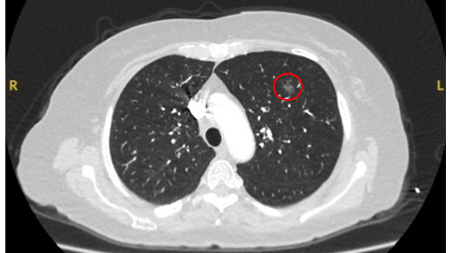

Computed tomography (CT) showing a posterior left upper lobe spiculated nodule, with ‘bronchus sign’ in a female non-smoker. Bronchoscopic forceps biopsy and brushing assisted by radial EBUS miniprobe localisation, confirmed a non-Hodgkin’s lymphoma

From the collection of Dr George Tsaknis, MD, PhD, FRCP(London), MRQA, MAcadMEd, PGCert; used with permission